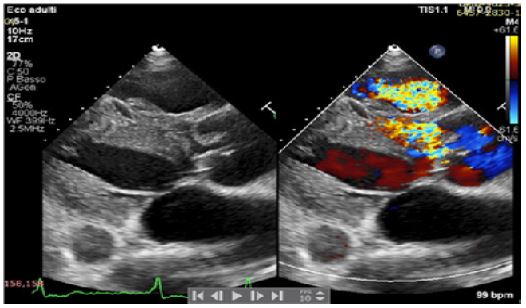

A 42-years old Senegalese man was referred to our department for dyspnea on exertion (NYHA II-III) and clinical signs of heart failure. In his clinical history an undefined cardiopathy, known since childhood but not investigated because asymptomatic, was reported. General examination revealed tachyarrhythmic pulse (rate of 103 per minute) along with normal blood pressure (130/65 mmHg) and arterial oxygen saturation (SpO2 97-99%). Electrocardiography demonstrated atrial fibrillation with left ventricular hypertrophy and signs of pressure overload (Figure 1), while chest X-Ray showed severe cardiomegaly and pulmonary congestion. Transthoracic Echocardiogram (TTE) with color Doppler revealed the presence of a 21 mm perimembranosus Ventricular Septal Defect (VSD), below the aortic valve, with relevant left-to-right shunt (gradient 90 mmHg), partially closed by prolapsing right coronary cusp and accessory tricuspid valve tissue (Figures 2 and 3). A hypertrophied muscle bundle in the mid-ventricular region of the Right Ventricle (RV) along with color-flow turbulence was documented (Figure 4). Due to misalignment, no accurate estimation of intraventricular RV pressure was feasible, but moderate tricuspid regurgitation revealed an atrioventricular gradient of 70 mmHg, suggesting high RV pressures. Other findings were severe aortic valve regurgitation with severe dilation of ascending aorta (diameters of sinuses of Valsalva 60 mm, 28 mm/m2, z-score +6,3, tubular ascending aorta 48 mm, 23 mm/m2, z-score +5,7). 2D and 3 D Transoesophageal Echocardiographic Examination (TOE) confirmed the presence of the anomalous muscle band dividing the RV into two parts: a high-pressure inlet portion and a lower pressure outlet portion (Figures 5 and 6). Severe dilation of both aorta and pulmonary trunk was revealed, confirming severe aortic valve regurgitation with multiple jets and determined by different factors (lack of coaptation, prolapse of the right cusp and distortion of the noncoronary cusp). To accurately measure RV pressures cardiac catheterization was performed. The systolic pressure of the right ventricular inlet and the outlet pressure were 78 and 38 mmHg respectively, determing an intraventricular gradient of 40 mmHg. There was no pressure gradient between the right ventricle outlet tract and the main pulmonary artery (systolic/diastolic/mean pressures were 38/18/25 mmHg respectively). Normal coronary arteries were documented. Patient was scheduled for corrective surgery in the form of resection of the anomalous muscle bundle along with patch closure of the VSD and Bentall procedure for ascending aorta or aortic valve replacement.

Figure 5: Transoesophageal echocardiographic examination.

Figure 6: Transoesophageal echocardiographic examination.